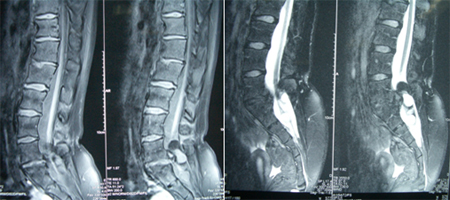

女性,17岁,劳累后腰部疼痛3年。入院查体:神情语利,卧位,双眼活动充分、双瞳等约2.0mm、光反射灵敏,面纹称,伸舌中,颈抵抗(-)。四肢可自主活动,鞍区针刺痛觉减退。B超:膀胱残余尿量10ml。术前图片:

术中发现L4-5椎板异常增生肥厚,L5椎板伸入椎管内形成骨嵴,脊髓圆锥低位在L4水平,L4以下肿瘤组织为多种成份,近端为脂肪组织,S1水平分为两种肿瘤成份,内侧为清亮粘液状物、外侧为珍珠样角化物。

术后病理结果为成熟性囊性畸胎瘤。术后图片